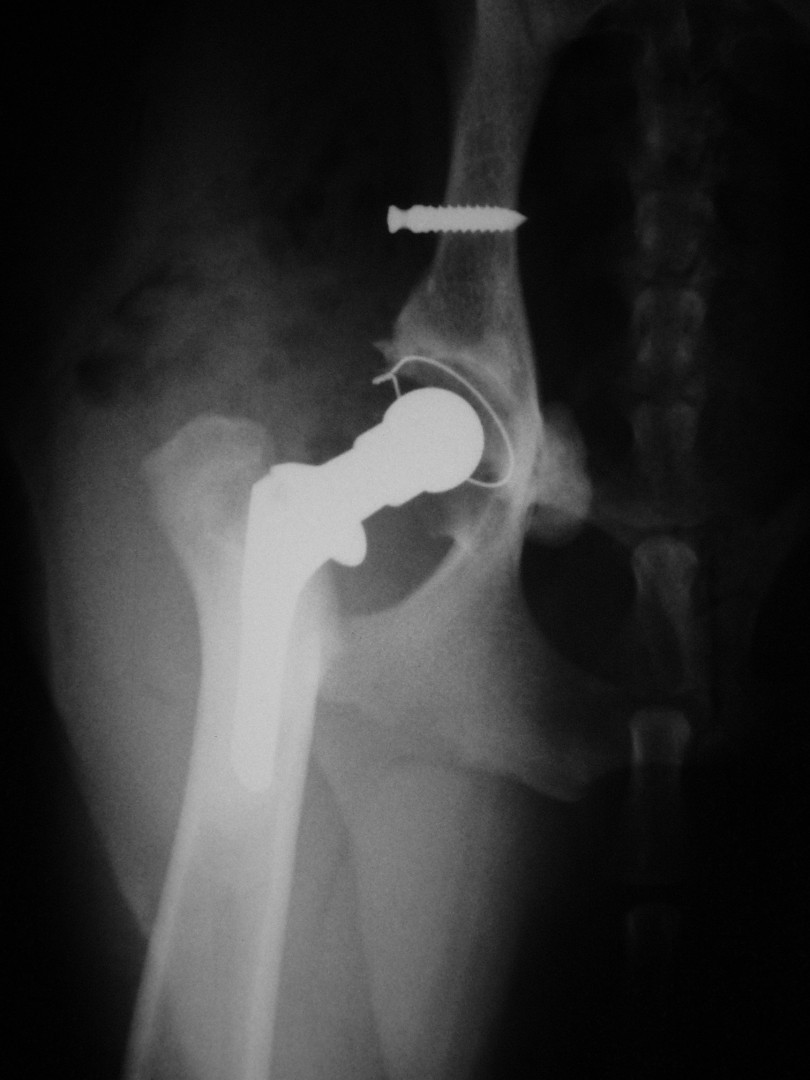

Teljes csípőízületi protézis

Bár a csípőízület megbetegedéseiről – mint a leggyakrabban tárgyalt ortopédiai megbetegedésről- első körben nem szerettem volna szólni, mégis megteszem, mert 2010. májusában egy hosszabb egyeztetést és szervezést követően beültettük az első teljes csípőízületi protézist…

A szervezés két részből állt: egyrészt felkerestük azt a magyarországi gyártót, aki a hazai anyagi lehetőségeket is figyelembe véve a szakmai szempontból is optimális rendszert le tudja gyártani, másrészt rábeszéltem Kendik Zsolt kollégámat, aki a hazai csípőízületi protézis beültetésének úttörője, hogy legyen segítségemre a műtét technikájának elsajátításában.

A tényleges műtét előtt temérdek teendő akad. A kutya teljes belgyógyászati kivizsgálása, egyéb ortopédiai és/vagy neurológiai betegségek kiszűrése, a tulajdonosokkal folytatott többszöri megbeszélés, a kockázatok mérlegelése és ezek részletes ismertetése jelentős energiát emészt fel. De ezek nélkül a beteg állat tulajdonosa nem tud reális döntést hozni: vállalható-e a műtét vagy sem?A műtéti időpont egyeztetése sem egyszerű: az operáció során 4 ember összehangolt munkájára, tökéletes aneszteziológiára és a műtétet követően az asszisztensek gondos munkájára van szükség a teljes gyógyuláshoz. Ez szintén jelentős szervezést igényel. A műtétet követő 10 napos kórházi ápolás és az ez utáni 3 hónapon át tartó szigorú mozgáskorlátozás betartása és betartatása a gyógyulás elengedhetetlen feltétele. Egy fiatal, ereje teljében lévő, energikus kutyánál ez néha nehezebb feladat, mint maga az operáció.

Az első műtét remekül sikerült és Connor, a skót juhász kutya megkapta a bal oldali új csípőízületét. A 7 napi kórházi tartás is problémamentesen zajlott és a varratszedés idejére a műtött végtag terhelése gyakorlatilag hibátlan volt. Az 1 hónapos és a 3 hónapos kontroll RTG vizsgálatokon sem jelentkezett szövődményre utaló jel, az 1 éves postoperatív időszakban már csak az látszott, hogy a műtött lábát jobban terheli, mint a nem operált végtagot. Így 2011. júniusában – immár sokadik csípőízületi protézis műtétként- a jobb oldali csípőízületét is megoperáltuk. Connor gyakorlatilag azóta teljes életet él és vidáman játszik társaival, még birkákat is terel…A majd két éves, a protetizálás során szerzett tapasztalatok azonban nálunk is hozzák a szakirodalomban leírt szövődményi lehetőségeket és arányokat. Leggyakrabban a beültetett protézis ficamával találkoztunk, de akadt sajnos kilökődési reakció is. Ezen problémák – az előzetes tájékoztatás ellenére is- mindig váratlanul érik a tulajdonost és az állatorvost egyaránt. Megoldásuk szinte kizárólag műtéti, ami újabb kockázatot, újabb fizikai és anyagi áldozatot jelent.